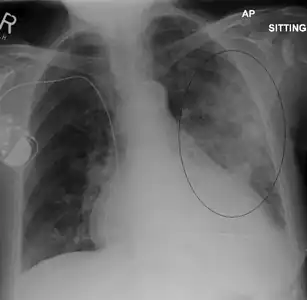

- AP CXR showing left lower lobe pneumonia associated with a small left sided pleural effusion

- Left upper lobe pneumonia with a small pleural effusion.